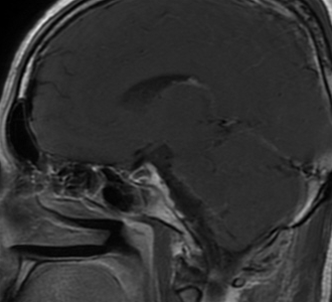

术前影像

入院后行术前检查,核磁共振显示:斜坡偏左占位,脑膜瘤可能性大。

左侧斜坡脑膜瘤